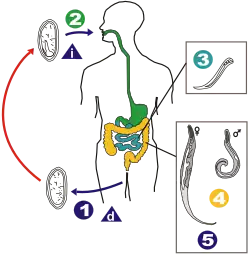

Ohne Zwischenwirtstadien gelangt das vom Wirt – eventuell inhalativ – aufgenommene Ei in den Magen, wo die Eihülle aufgeweicht wird. Aus dem Ei entwickeln sich schon nach sechs Stunden die ersten Larven. Im Zwölffingerdarm schlüpfen die Larven aus der Eihülle und häuten sich.[5] Diese wandern vom Dünndarm, wo sie sich bis zu dreimal häuten, zum bevorzugten Aufenthaltsort an der Darmwand rund um den Blinddarm. Dort saugen sie sich an der Darmwand fest[3] und bilden mit ihrem Wirt eine Kommensale (Fressgemeinschaft). Hier wachsen die Tiere etwa zwei bis drei Wochen lang aus und erreichen die Geschlechtsreife.

Nach der Paarung sterben die Männchen. Die Weibchen wandern nach der Paarung und einer etwa zweiwöchigen Reifung der Eier zur Eiablage in Richtung After. Vorwiegend nachts kriechen sie aus dem After heraus, legen binnen 10 bis 30 Minuten ihre Eier (5.000 bis 17.000[7]) an den Anusfalten ab, und sterben danach. Die Eier enthalten bereits einen kaulquappenförmigen Embryo,[3] der sich nach Ablage zum zweiten Larvenstadium weiterentwickelt. Bei Sauerstoffzutritt im Freien werden die Eier schon innerhalb weniger (4 bis 8) Stunden infektiös.[8][7][4][5] Diese vergleichsweise sehr schnelle Entwicklung bezieht ihre Energie im Wesentlichen aus gegenüber Fett schnell abbaubaren Glykogenvorräten, die im mittleren und hinteren Körperbereich der Würmer konzentriert sind, wo in dieser Entwicklungsphase auch die meiste Ausdifferenzierung und Bewegung stattfindet.[9]

Beim Kratzen in der Perianalgegend können an den Fingern, besonders unter den Nägeln, Eier haften bleiben, die durch Anus-Finger-Mund-Kontakt oft vom Wirt selber wieder aufgenommen werden, wodurch es zu erneuter Infektion kommt (Selbstinfektion). Ansonsten ist der wichtigste Ausbreitungsweg das Verstäuben der winzigen Eier durch die Luft mit schließlicher Aufnahme über kontaminierte Nahrung oder Inhalation aufgewirbelter Eier. Manche Autoren vertreten die Meinung, dass bereits am After geschlüpfte Larven auch direkt in den Darm kriechen können.[10] Die Eier des Madenwurms sind bis zu drei Wochen ansteckend.